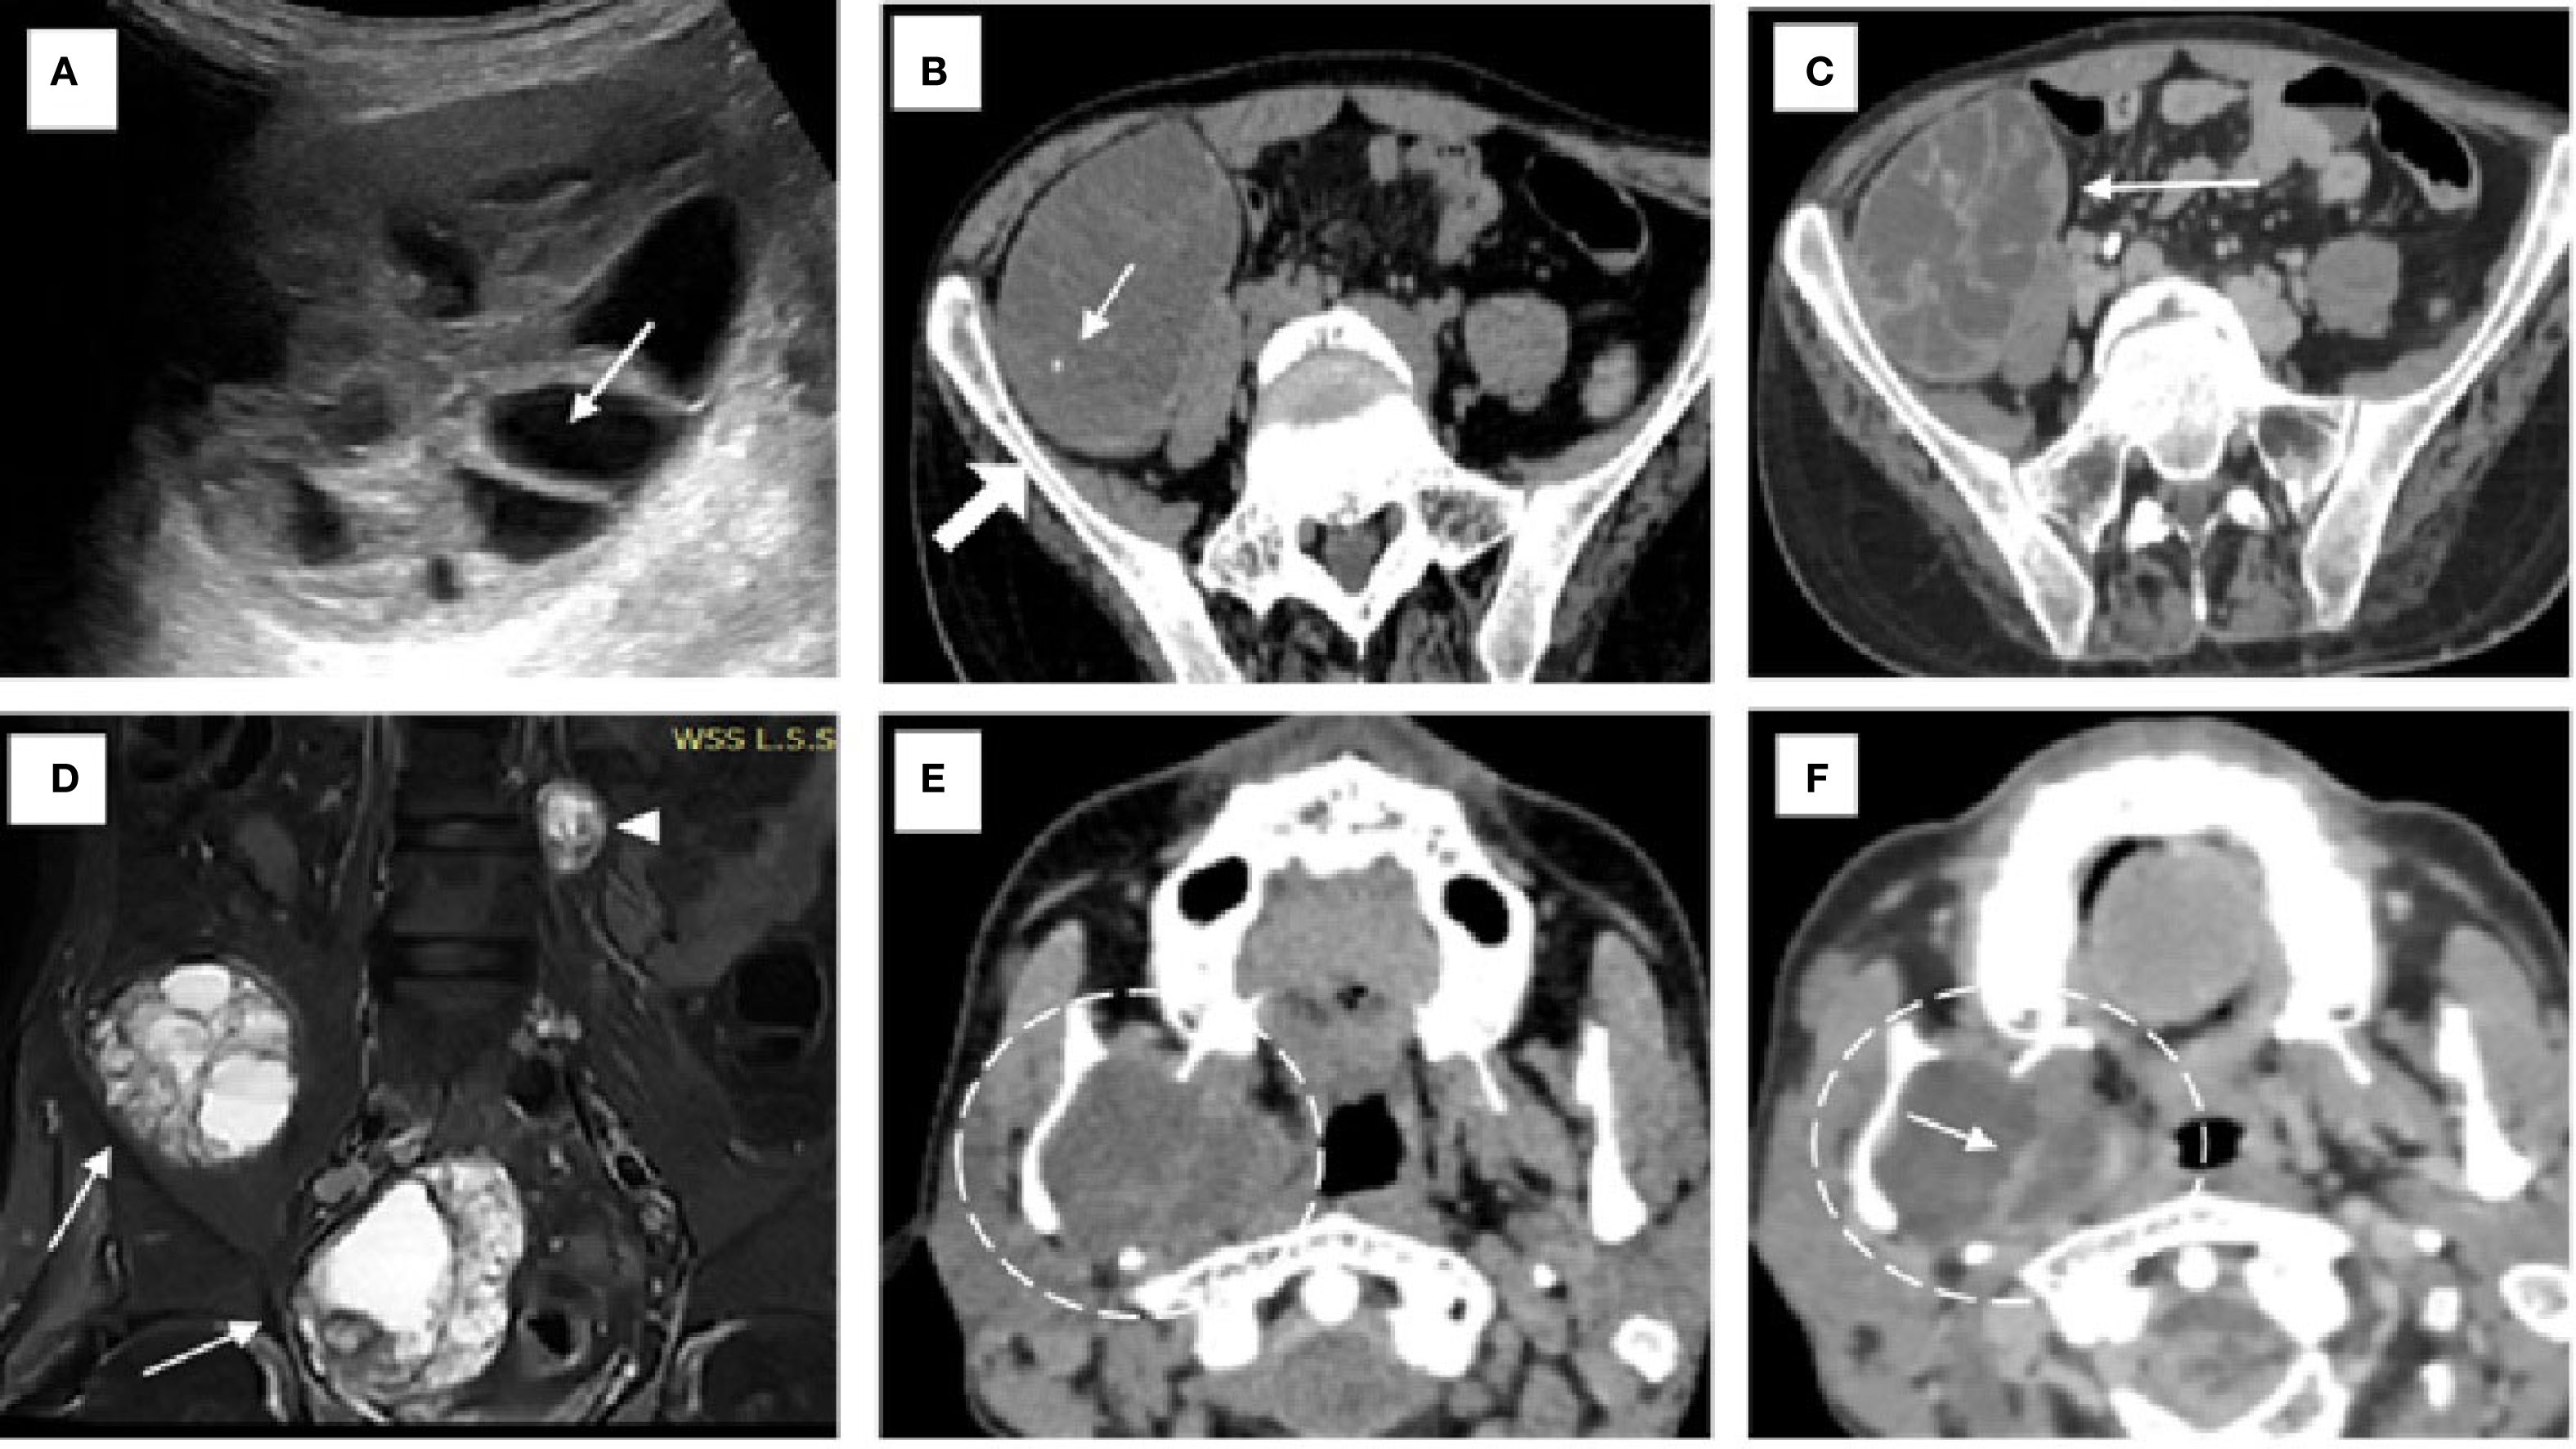

The patient initially underwent an ultrasound of the abdomen and other symptomatic regions, which revealed multiple (from four to five) well-defined, thick-walled cystic lesions in the pelvis (Figure 1A), the largest along the iliac bone measuring 5.3 cm × 6.5 cm × 7 cm [anteroposterior (AP) × transverse diameter (TD) × craniocaudal (CC)]. These cysts showed daughter cysts in a spoke-wheel pattern and hydatid sand, consistent with CE2 active-stage hydatid disease. Additional cystic lesions were identified in the suprasternal region, the anterior chest wall, the extensor compartments of both arms, and the right thigh. A contrast-enhanced computed tomography (CECT) confirmed these findings, demonstrating internal septations, daughter cysts, and septal calcifications in the pelvic cavity (Figures 1B, C), infraclavicular regions, pleura, and extremities (Figures 2A, B). Intraosseous cysts were also seen in the ramus and angle of the right mandible, measuring 3.4 cm × 4 cm × 3.4 cm (AP × TD × CC) (Figures 1E, F), showing a calcified rim without daughter cysts, corresponding to CE5 inactive cysts. CT additionally revealed multiple cysts at the craniovertebral junction, the cervical spine, and the dorsal spine, all showing peripheral rim enhancement, but no pericystic inflammation.

Figure 1. Imaging findings of hydatid disease involving the pelvis and mandible. (A) On ultrasound, a hydatid cyst is seen in the pelvis with multiple internal daughter cysts (white arrow). (B) Non-contrast axial CT image confirming the presence of a hydatid cyst with multiple daughter cysts and showing areas of septal calcification (white arrow) adjacent to the iliac bone (solid white arrow). (C) Axial post-contrast CT revealing peripheral and septal enhancement (white arrow), which is characteristic of an active hydatid cyst classified as WHO type CE2. (D) Coronal short tau inversion recovery (STIR) MRI image of the pelvic cavity (D) demonstrating multiple hydatid cysts of varying sizes located within the pelvic cavity (white arrows) and the left paravertebral region (white arrowhead) of the lumbar spine. (E, F) Non-contrast (E) and contrast-enhanced (F) CT images of the neck showing an intraosseous hydatid cyst (dashed white circle) with internal septations involving the ramus and angle of the right mandible, resulting in medial displacement of the medial pterygoid muscle. Rim and septal enhancement is seen on the post-contrast image [white arrow in (F)].